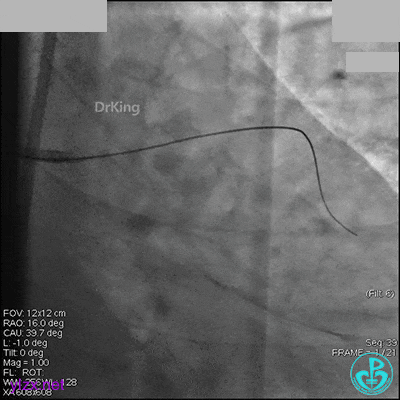

AL 1.0指引导管到位,简单短时尝试导丝不能顺利通过前降支或回旋支病变。改变策略处理右冠脉病变,计划植入2枚支架。AL指引导管到位,Sion blue导丝到达右冠脉远端。导丝通过后1.5mm及2.5mm球囊14~16atm充分扩张中段病变。

右冠脉中段充分扩张后欲植入3.5×38mm支架时,支架难以通过中远段扭曲处,且指引导管、导丝弹出飞扬。反复尝试导丝重新到达右冠脉远端时通过不顺利,局部造影剂滞留,远端血流接近3级。